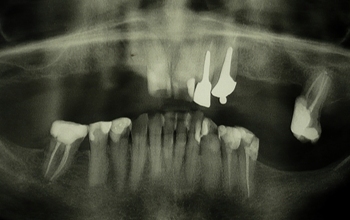

Rentgenska slika pacientke pred izdelavo delne proteze. |

Za boljši oprijem in stabilnost nove proteze smo pacientki vstavili strateški implantat. |